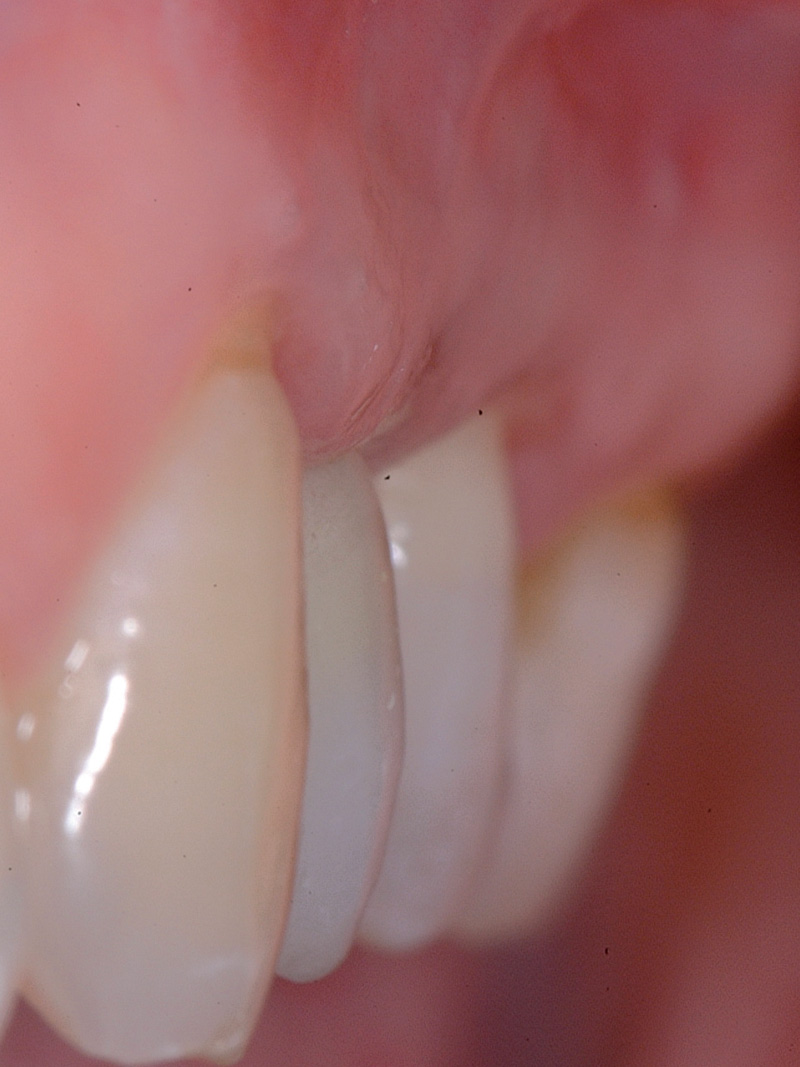

Dopo 4 settimane dall’estrazione si è proceduto in un unico appuntamento ad eseguire la scansione intraorale (Fig. 4) e, su questa, la ceratura virtuale dell’area edentula (Figg. 5, 6), la Rx endorale (Fig. 7) e l’esame TC Cone Beam (Fig. 8); infine si è effettuato il matching dei due dati digitali (Fig. 1) e si è scelto tipo e posizione dell’impianto. Come si può notare dalle immagini, a sole 4 settimane dall’estrazione il sito presentava insufficiente disponibilità, mostrando soprattutto la completa assenza della corticale vestibolare. La pianificazione del caso prevedeva, nonostante la presenza della dima chirurgica per il posizionamento dell’impianto, l’apertura di un lembo chirurgico per rigenerare contestualmente la componente ossea vestibolare.

Si noti il condizionamento del tessuto gengivale, con la convessità vestibolare e il rispetto di una parabola corretta per la maturazione delle papille interdentali (Figg. 28-30).

- Fig. 28 – Profilo concavo del tessuto gengivale vestibolare prima del posizionamento implantare

- Fig. 29 – Profilo convesso del tessuto gengivale vestibolare al momento della consegna del provvisorio